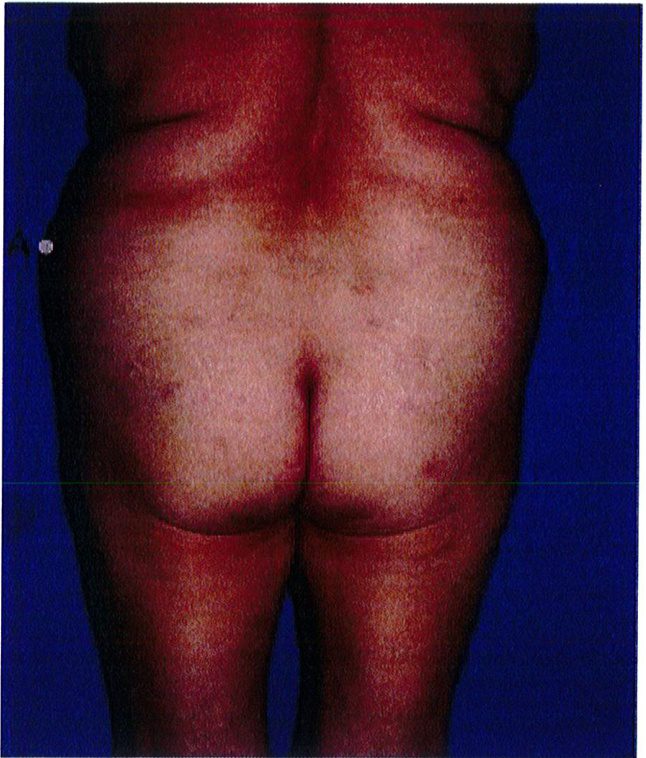

Lý do chính để đảnh giá độ đàn hồi da là để xác định xem có cần nâng mông trên hoặc cắt bỏ vùng da thừa ở nếp lắn mông hay không để tái tạo đường cong thẩm mỹ. Da thừa nhiều thường xuất hiện ở bệnh nhân sau MWL (Hình 26). Nếu da chảy xệ ở vùng chứa điểm B hoặc C thì có thể chỉ định làm thủ thuật nâng mông. Chỉ định khác để thực hiện nâng mông là bệnh nhân có tình trạng lõm nặng ở điểm C, tuy nhiên, việc chuyển mô mỡ từ vùng khác qua cũng có thể xem xét để thực hiện. Luôn nhớ rằng độ lõm tại điểm C càng lớn thì khả năng bệnh nhân cần thực hiện nâng mông càng lớn theo.

Square shape

Hình. 26. (A) Đánh giá độ chùng của da mông ở các vị trí với các hình dạng khác nhau. Bệnh nhân bên trái bị lõm nghiêm trọng ở điểm C và vùng ngoài da tương đối sần sùi. Cô ấy nên được điều trị bằng các pp nâng mông. 3 bệnh nhân còn lại xuất hiện vùng da thừa và nếp nhăn ở điểm B và C. (B) Bệnh nhân ở ảnh ngoài cùng bên phải của hình 26A sau khi trải qua phẫu thuật nâng mông trên bằng vạt da. Ở thì hai của cuộc phẫu thuật, cô ấy đã được nâng nếp lằn mông và làm đầy bằng implant.